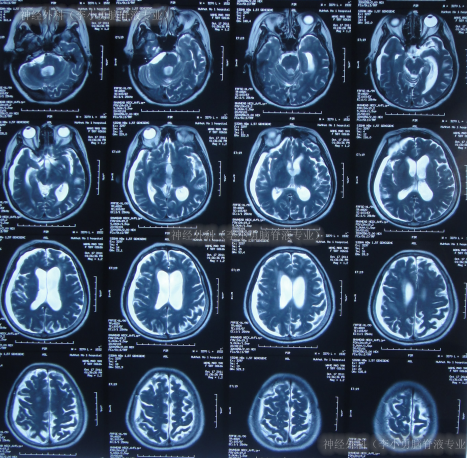

又过2月后即2011年10月14日,夜里2点起夜时突然站不稳,再次出现头昏,呕吐频繁,四肢无力,2011年10月17日第2次就诊于第2家医院:呼和浩特市某医院神经内科住院治疗,行头颅MRI(图-1)认为“末梢神经脱髓鞘病变,考虑为格林巴利综合征,轻度脑积水”。

图-1:2011年11月17日头颅核磁